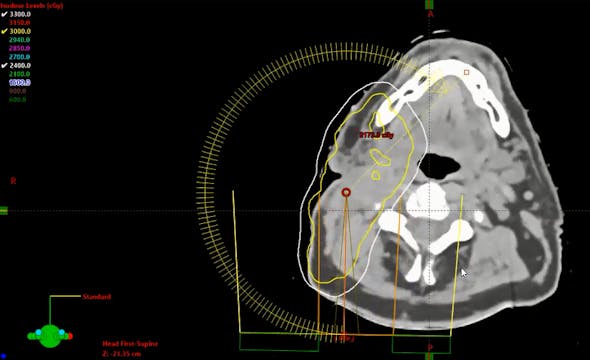

04/13/21 - Dr. Kenneth Hu - Radiation Oncology - Head and Neck

Neck mass carcinoma, unknown primary, tonsillectomy, neck dissection and rapid lymph node regrowth, dose, treatment fields, de-escalation for HPV